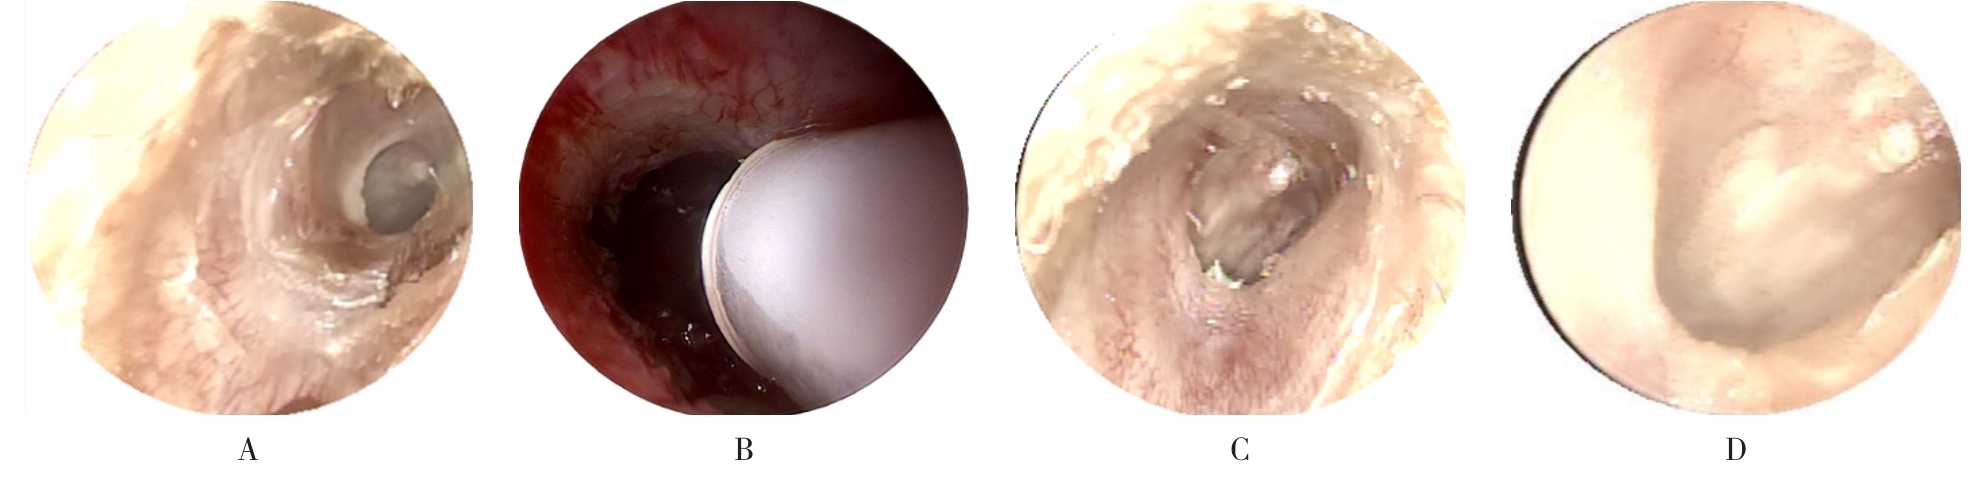

摘要:目的 分析医用生物蛋白胶应用于耳内镜下鼓膜修补术的临床疗效。方法 回顾性分析2022年10月-2023年10月该院收治的60例单纯鼓膜穿孔患者的临床资料,根据手术方法不同,将患者分为研究组和对照组,各30例。研究组术中使用医用生物蛋白胶粘合残余鼓膜和修补材料;对照组术中采用明胶海绵覆盖修补鼓膜。观察两组患者术后的鼓膜愈合情况(鼓膜愈合率、愈合时间、干耳时间和外耳道上下径)和并发症发生情况;于手术前后,采用纯音测听法(500、1 000、2 000、4 000 Hz),测量两组患者气导阈值,观察听力改善程度;采用视觉模拟评分法(VAS)评分,评估患者术后疼痛程度。结果 两组患者术后鼓膜愈合率、愈合时间、外耳道上下径和并发症发生率比较,差异均无统计学意义(P > 0.05)。研究组术后平均气导听阈明显低于对照组,差异有统计学意义(P < 0.05)。研究组术后干耳时间短于对照组,术后第1天疼痛VAS评分明显低于对照组,差异均有统计学意义(P < 0.05)。结论 医用生物蛋白胶应用于耳内镜下鼓膜修补术,可有效地降低气导听阈,缩短干耳时间,减轻患者疼痛,且不增加并发症发生率,值得临床推广应用。